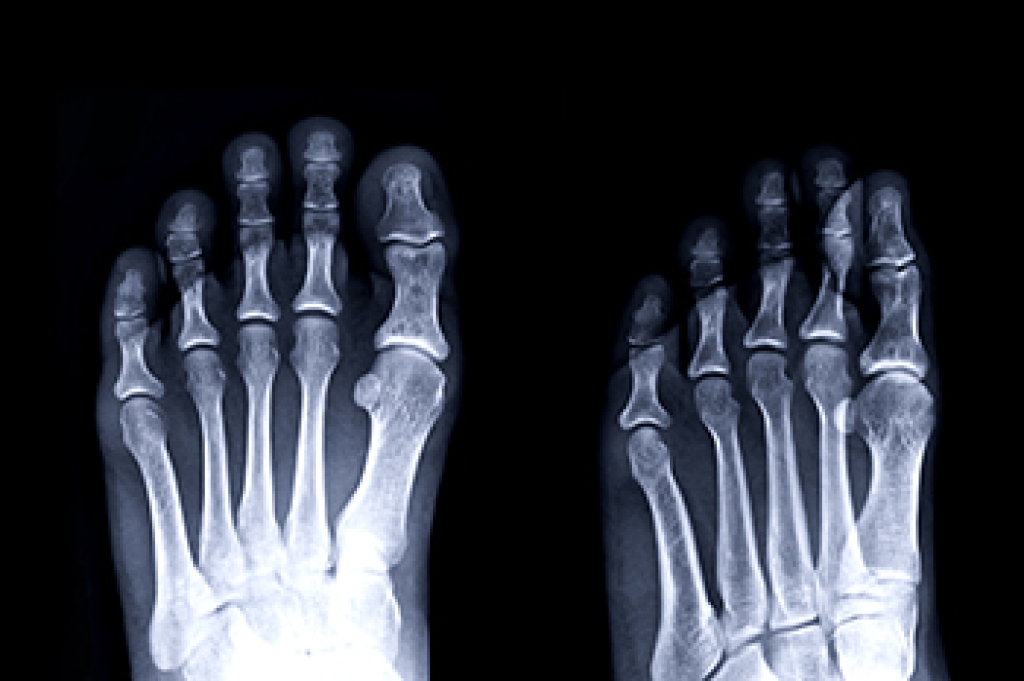

A physical exam of the leg can help identify the presence of tarsal tunnel syndrome. Medical tests, such as a nerve biopsy, are also used to diagnose the condition. Patients may receive physical therapy and prescriptive medication. In extreme cases, some may require surgery.